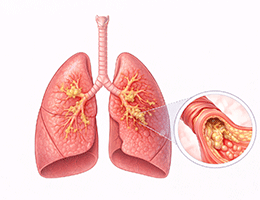

폐렴 (Pneumonia)

기관지염 (Bronchitis)

천식 (호흡기계 (기관지, 폐))

폐결핵 (Pulmonary Tuberculosis)

만성폐쇄성폐질환 (Chronic Obstructive Pulmonary Disease)

폐기종 (Emphysema)

폐농양 (Lung Abscess)

폐혈증 (Pulmonary Sepsis)